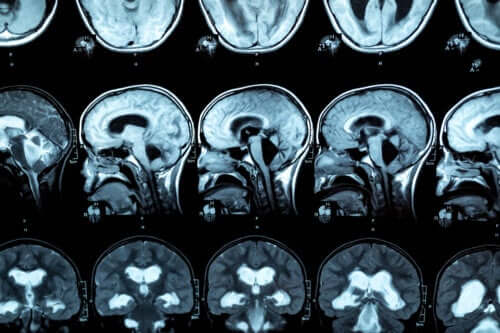

Le gonflement du corps calleux peut également être apprécié sur l’imagerie cérébrale. Dans certains cas, des signes de syndrome de déconnexion interhémisphérique sont présents.

Pour le diagnostic de cette pathologie, une IRM est réalisée, afin que les lésions du corps calleux puissent être observées. La recherche indique que les personnes souffrant de troubles liés à la consommation d’alcool présentent une réduction de l’épaisseur antérieure, moyenne et postérieure du corps calleux, ainsi que des variations de la taille du lobe frontal et des sillons corticaux.